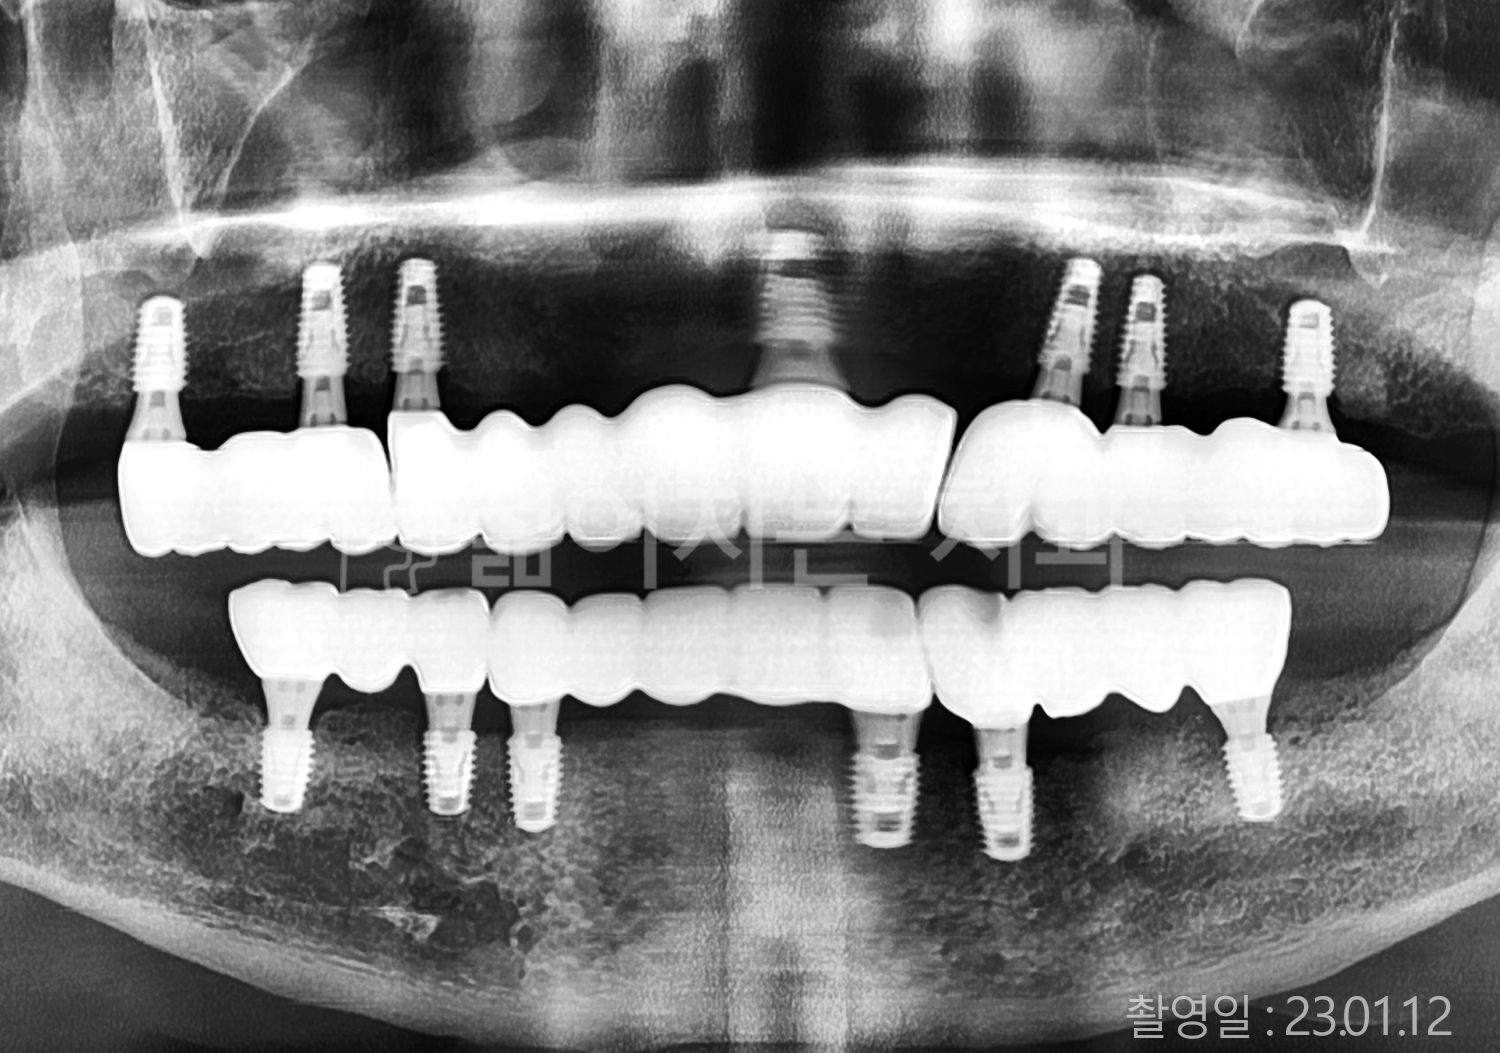

• 70대 고혈압, 고지혈증 전체치아 10개 이상 임플란트

• 60대 당뇨, 간염 전체치아 10개 이상 임플란트

• 80대 골다골증 전체치아 6개 이상 임플란트

• 70대 고혈압, 당뇨 전체치아 10개 이상 임플란트

• 60대 간 질환 전체치아 10개 이상 임플란트

• 60대 전체치아 10개 이상 임플란트

• 70대 전체치아 10개 이상 임플란트

• 50대 전체치아 10개 이상 임플란트

• 60대 고혈압, 고지혈증 전체치아 10개 이상 임플란트

• 40대 고지혈증, 뇌혈관 질환 전체치아 10개 이상 임플란트